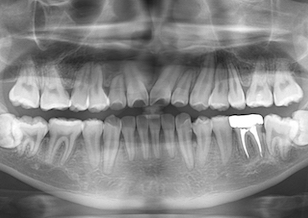

レントゲン所見では、 右側上顎犬歯と第1小臼歯、第2小臼歯の3本が埋伏しております。右側上顎犬歯は隣の側切歯の歯根を圧迫し側切歯の歯根吸収を引き起こしており今後更なる歯根吸収の可能性が考えられました。

一般的には埋伏歯を放置しておいた場合、隣在歯の歯根吸収(歯冠が他の歯の歯根を圧迫することにより、歯根が溶けてしまうこと)が起こる場合があるので早めの対策が必要です。

BeforeⅠは、治療前のパノラマレントゲンです。

AfterⅠは、治療終了時のパノラマレントゲンです。